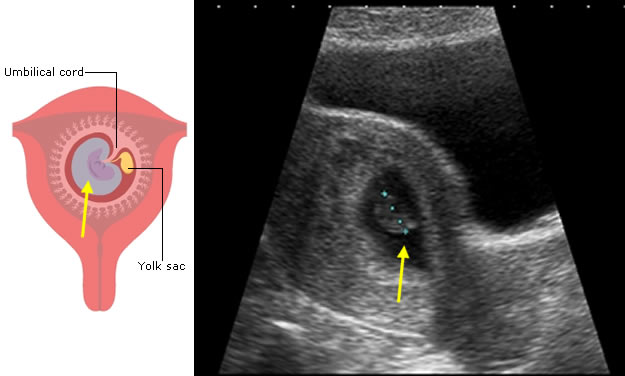

The first feature to be seen on ultrasound is the gestation sac, which will become the amniotic and chorionic sacs. These contain fluid and are seen as black on ultrasound.

The trophoblast is specially modified embryonic tissue which allows the pregnancy to implant into the uterine wall. It is almost white on ultrasound and part of it will form the placenta.

The embryo itself is usually only seen after 6 weeks following the last period.

Note: in this ultrasound image of an early pregnancy, the sonographer has made a measurement of the length of the developing baby (dotted blue line). You will learn about this measurement later in this session.